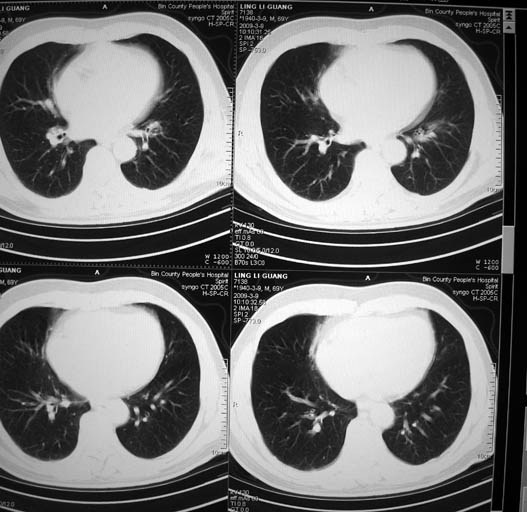

以下是引用随光逐影在2009-3-9 21:36:00的发言:[br]1)两肺上叶尖段结节状病灶,性质待定(不排除肿瘤可能);建议追踪复查。2)右肺中叶内侧段炎症。